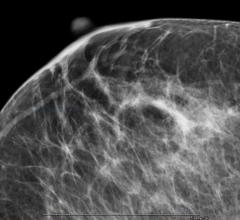

Despite decades of progress in breast imaging, one challenge continues to test even the most skilled radiologists ...

November 10, 2021 — DenseBreast-info.org (DB-I) commemorates the 10-year anniversary of the FDA’s National Mammography ...

Prologue In 2014, Imaging Technology News (ITN) introduced breast cancer survivor-turned-crusader Nancy Cappello, Ph.D ...